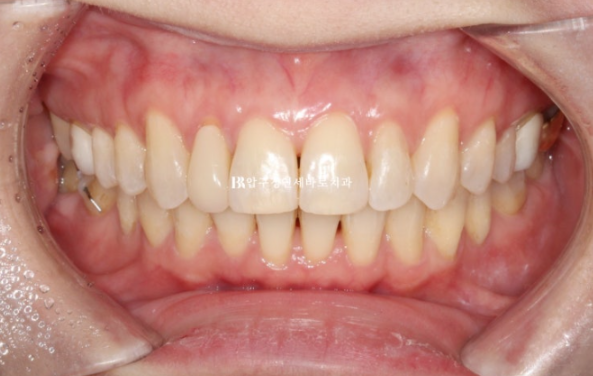

치료 마무리 후 모습입니다.

앞니가 깊게 물리는 과개교합이 개선이 되었습니다.

치간삭제로 블랙트라이앵글 사이즈를 줄일 수는 있지만 치간삭제가 과도하면 안되어서 소량의 블랙트라이앵글은 남았습니다.

치료 전 후 보겠습니다.

좌 - 치료 전 / 우 - 치료 후